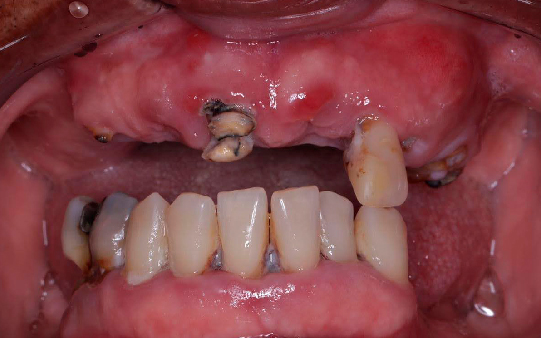

Problemas para se alimentar ou saborear alimentos

Problemas fonéticos e sistêmicos de saúde